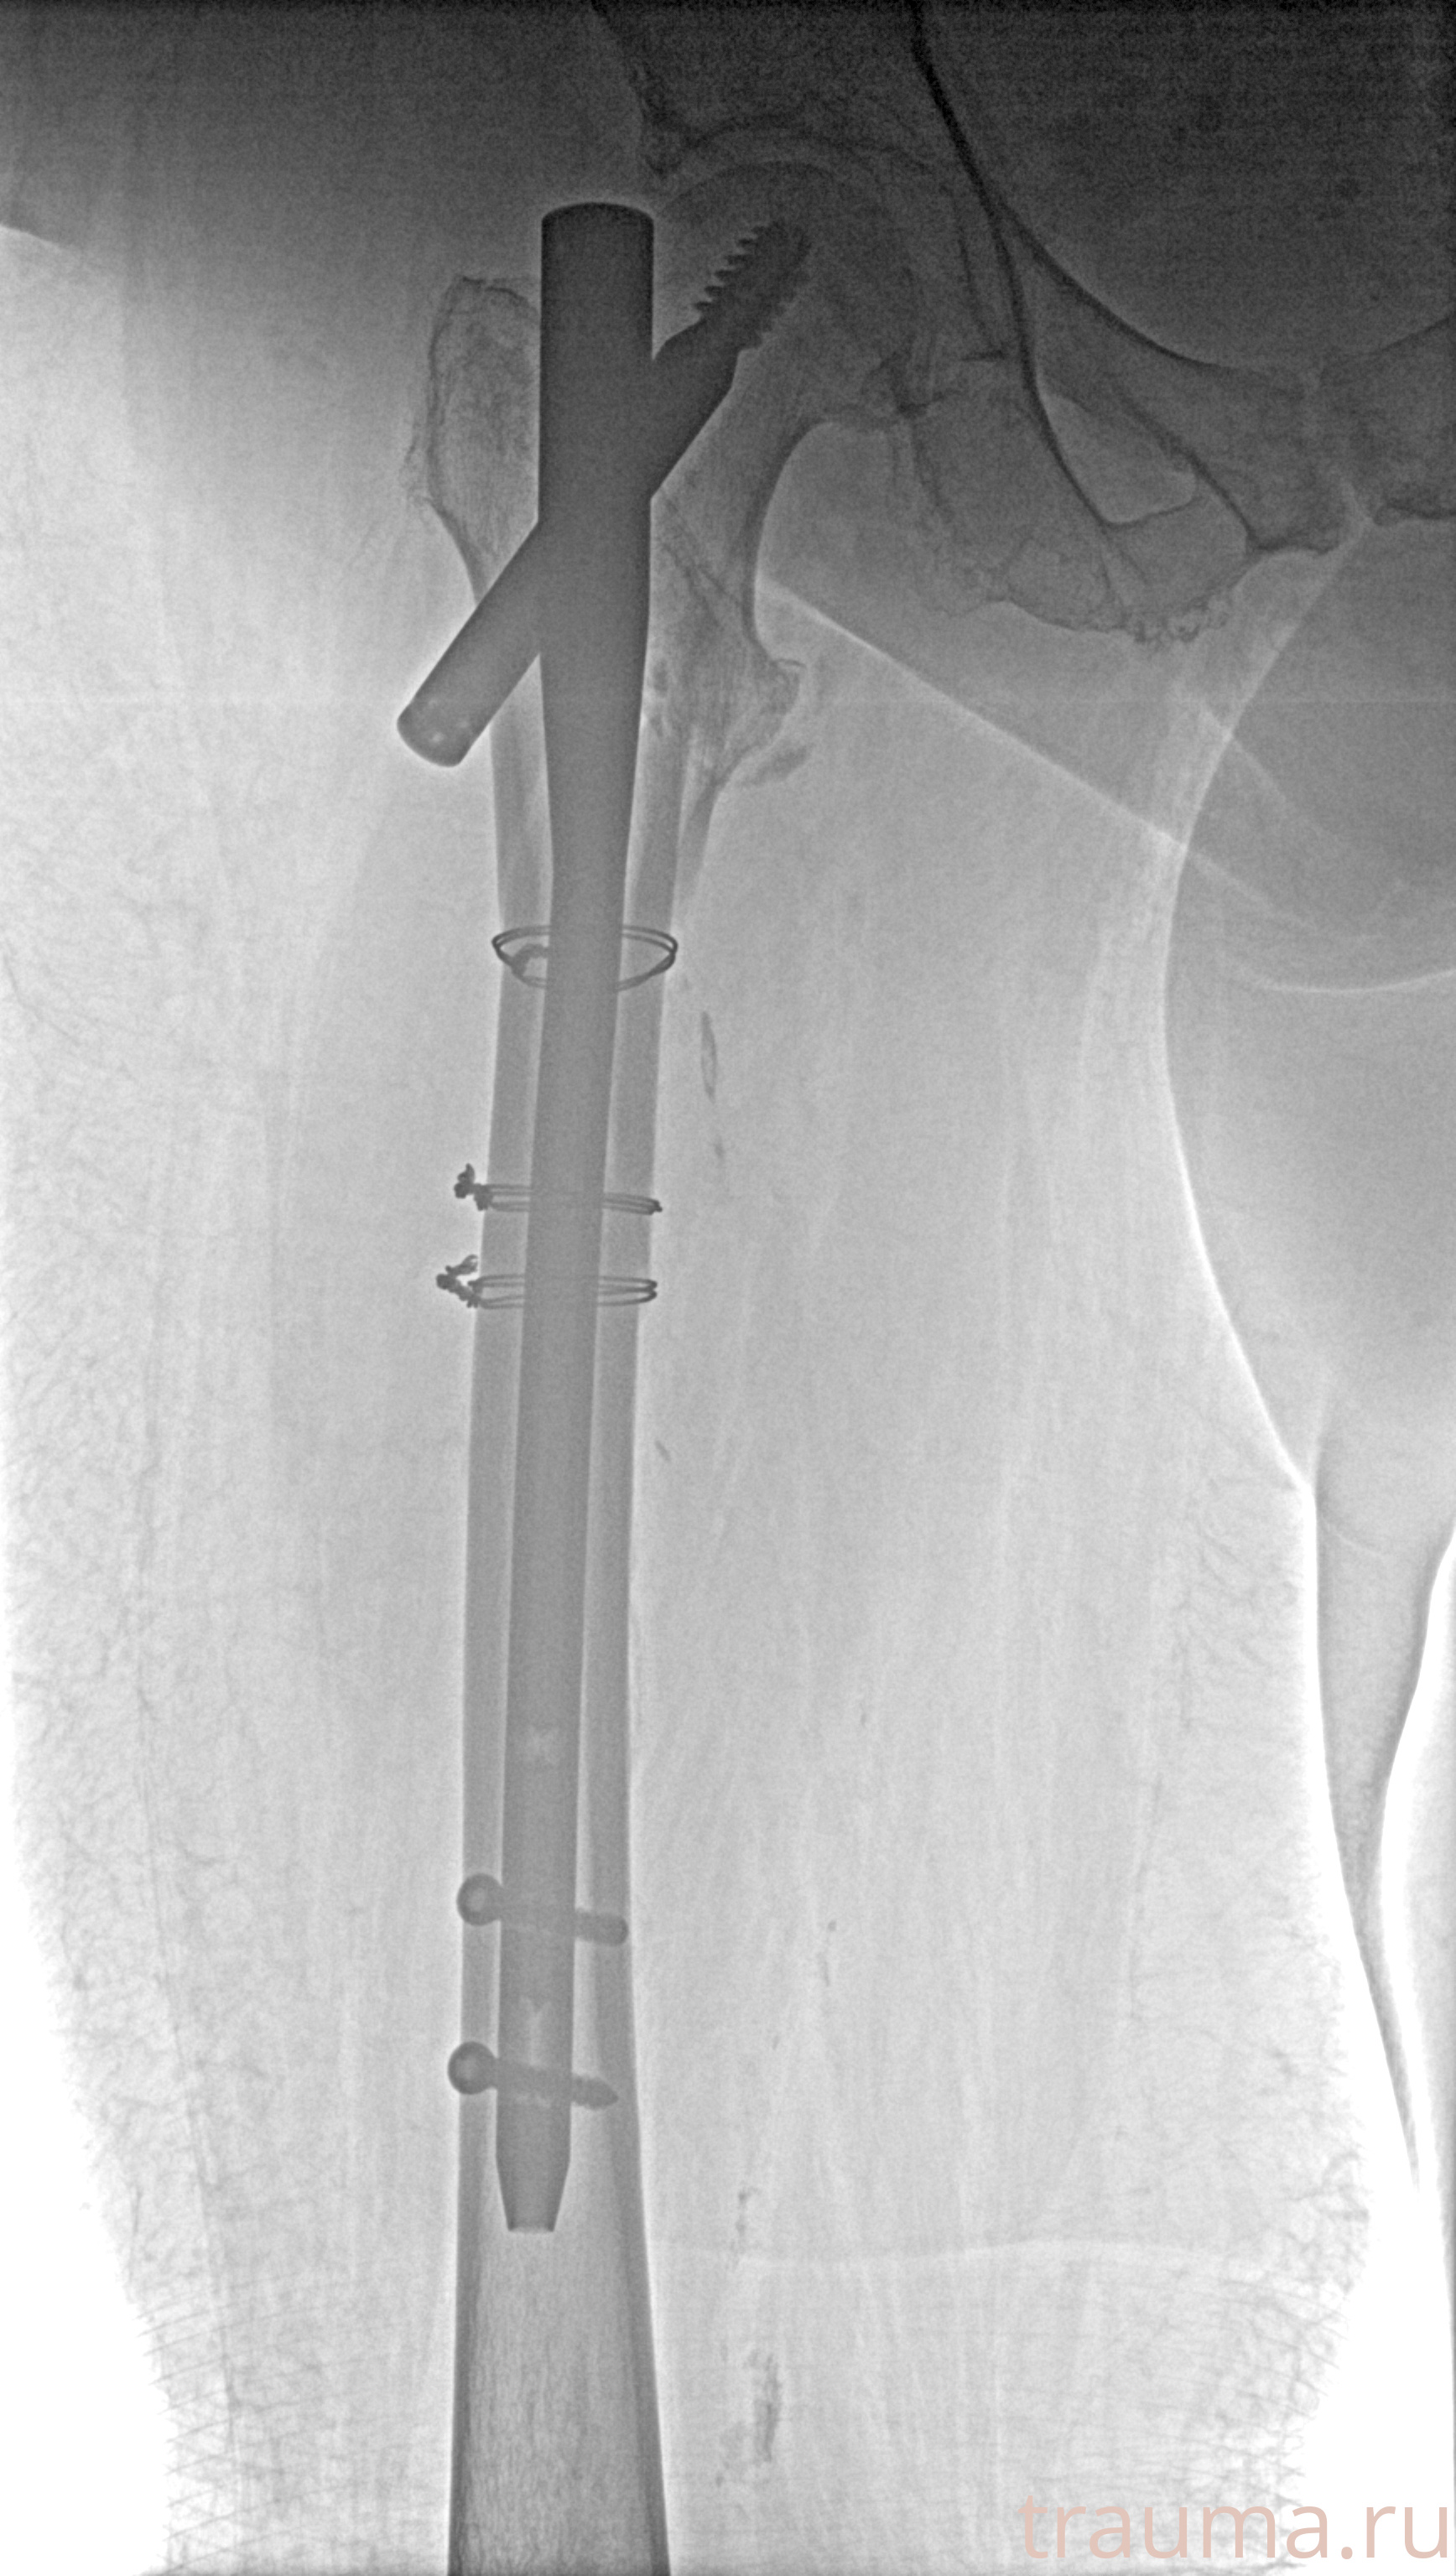

Рентгенограммы

Рентген на дому: по вашему адресу приезжает врач-рентгенолог, травматолог-ортопед с мобильным рентгеновским аппаратом, проводит диагностику травмы или заболевания, делает необходимые рентгенограммы, дает рекомендации по дальнейшему лечению. Получить качественные снимки в домашних условиях возможно благодаря уникальной методике, разработанной МосРентген Центром для института  Склифосовского